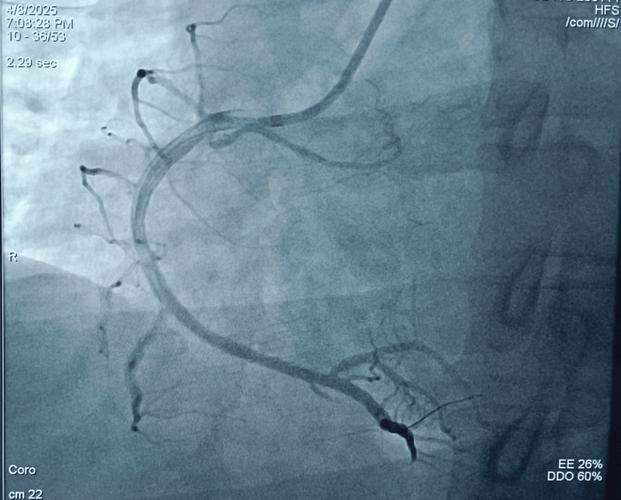

脑梗(缺血性脑卒中)和心梗(心肌梗死)患者进行冠状动脉造影(简称“冠脉造影”或“造影”)的可行性和安全性,需要根据患者的具体情况,由医生进行个体化的判断。

对于心梗患者,冠脉造影不仅是可以做的,而且是非常必要和常规的检查和治疗手段。

- 明确病因: 心梗的根本原因是冠状动脉(给心脏供血的血管)被血栓堵塞,造影可以直观地看到哪一根血管堵了、堵了多严重、是什么类型的病变(比如是急性血栓还是慢性狭窄)。

对于心梗患者,尤其是急性心梗,冠脉造影是挽救生命、开通血管的“金标准”,其获益远远大于风险,是必须尽快进行的检查和治疗。